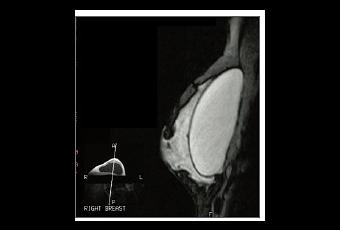

IMPLANTS MAMMAIRES et ruptures silencieuses, l'IRM n'est pas infaillible –